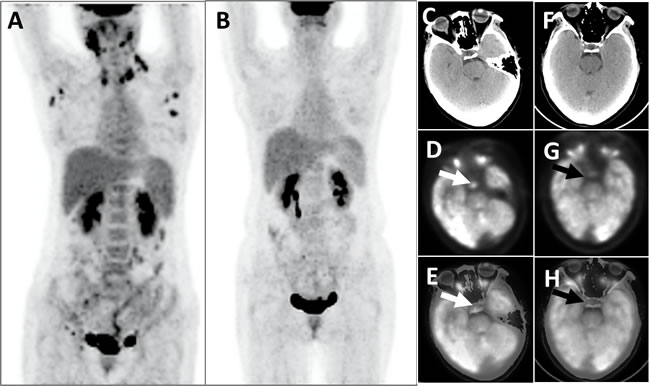

The three patients with LCH had an SUVmax ranged from 6.0 to 26.0 (15.0 ± 10.2). In addition to pituitary hypermetabolism, one patient had concurrent diffuse thyroid hypermetabolism, with a postoperative residual thyroid SUVmax of 11.3 (Figure 1). The second patient was found multiple hypermetabolic lymph nodes in the bilateral submandibular regions, neck, armpits, abdomen, retroperitoneum, pelvis, and bilateral groins, with SUVmax ranged from 2.0 to 13.2 (Figure 2). In addition to multiple hypermetabolic lymph nodes in or around the neck, hilar and mediastinum, retroperitoneum, iliac vessels, and groin (SUVmax = 15.6~18.9), the third patient also had concurrent thyroid hypermetabolism (SUVmax = 7.7), spleen enlargement and hypermetabolism (SUVmax = 8.0), local bone destruction and hypermetabolism (SUVmax = 8.7) around the left iliac wing and left pubis [1]. All the three patients had a definitive diagnosis established via a pathological examination based on other tissues’ biopsy other than pituitary.

Figure 2: This patient with LCH developed multiple hypermetabolic lymph nodes, which disappeared after chemotherapy. The PET whole-body images (MIP), taken prior to chemotherapy, showed that the patients displayed multiple abnormal FDG hypermetabolism (SUVmax = 4.4-13.2) of the lymph nodes in the bilateral submandibular areas, neck, armpits, abdomen, retroperitoneum, pelvic cavity, and bilateral inguinal areas A.; Post-chemotherapy PET whole-body images did not identify aberrant FDG hypermetabolic foci B. Head PET D. and G., CT C. and F. and PET/CT fusion topographic images (E and H) revealed that the pituitary exhibited apparent FDG hypermetabolism (white arrows, SUVmax = 6.0) before chemotherapy and that the metabolic activity was clearly decreased after chemotherapy (black arrows, SUVmax = 3.6).